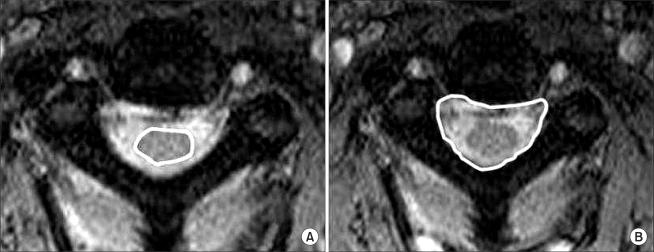

METHODS

A total of 212 cervical spinal levels in 53 patients with a distractive-extension injury were examined. The following four parameters were measured: Pavlov's ratio on the plain lateral radiographs, the sagittal diameter, the spinal cord area, and the spinal canal area on the MRI scans. The Pearson correlation coefficients between the parameters at each level and between the levels of each parameter were evaluated. The correlation between the radiological parameters and the spinal cord injury status classified into four categories, A (complete), B (incomplete), C (radiculopathy), and D (normal) was assessed.

The mean Pavlov's ratio, sagittal diameter, spinal cord area and spinal canal area was 0.84, 12.9 mm, 82.8 mm(2) and 236.8 mm(2), respectively. An examination of the correlation between the radiological spinal stenosis and clinical spinal cord injury revealed an increase in the values of the four radiological parameters from cohorts A to D. Pavlov's ratio was the only parameter showing statistically significant correlation with the clinical status (p = 0.006).